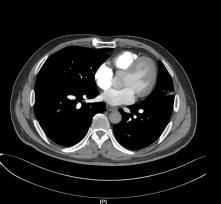

▎肺部增强CT(图片如下)

2.右上肺尖段少许慢性炎症;

3.纵隔多发肿大淋巴结,拟反应性增生,建议随诊;

4.拟左上肺多发体-肺动脉分流形成;

5.支气管动脉重建示左侧支气管动脉稍增粗。

反复阅读肺部CT并与影像科同事联系,患者肺部CT提示间质水肿、左肺上静脉显示不清,结合患者存在射频消融史,需要考虑肺静脉狭窄引起的咯血。

送入猪尾巴导管至双肺动脉造影示,左肺动脉造影见左上肺外周血管未显影,未见左上肺静脉回流,左下肺动脉显影良好,左下肺静脉回流尚好。

右肺动脉造影见右上肺动脉显影好,右上肺静脉回流尚可,进入左心房入处狭窄,约30%,右下肺动脉显影好,右下肺静脉回流尚可。超选LA1支造影显示左上肺静脉回流至左房入口处明显狭窄,约90%,左肺静脉回流处血管团造影剂渗出。

其中肺静脉增强CT检查及血管三维重建诊断PSV效果明显,该例患者我院首先完善了肺部动脉增强CT,影像科医生在报告中未报左肺静脉异常,我们反复阅读片子发现左肺静脉异常,从而进一步行右心导管、左心导管、肺动脉造影术,以此明确诊断;而使用心脏彩超诊断PVS中需警惕因操作者主观因素导致的诊断遗漏,注意加强与辅助科室之间的提醒。